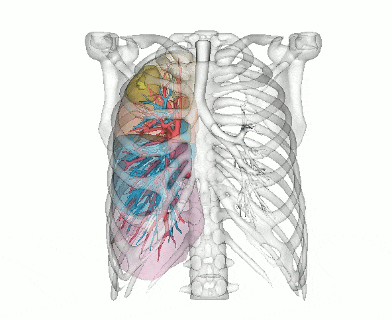

(三维重建中肺结节位置信息)

(三维重建肺动静脉预览)

(三维重建肺动静脉及肺段整体预览)

(肺段体积评估分析)

阿梵D三维重建后,患者肺部的支气管、血管、结节被转化为1:1还原的立体模型。医生通过旋转、放大模型,清晰看到结节与两支支气管的毗邻关系,基于这一精准可视化数据,医生可以快速制定方案。